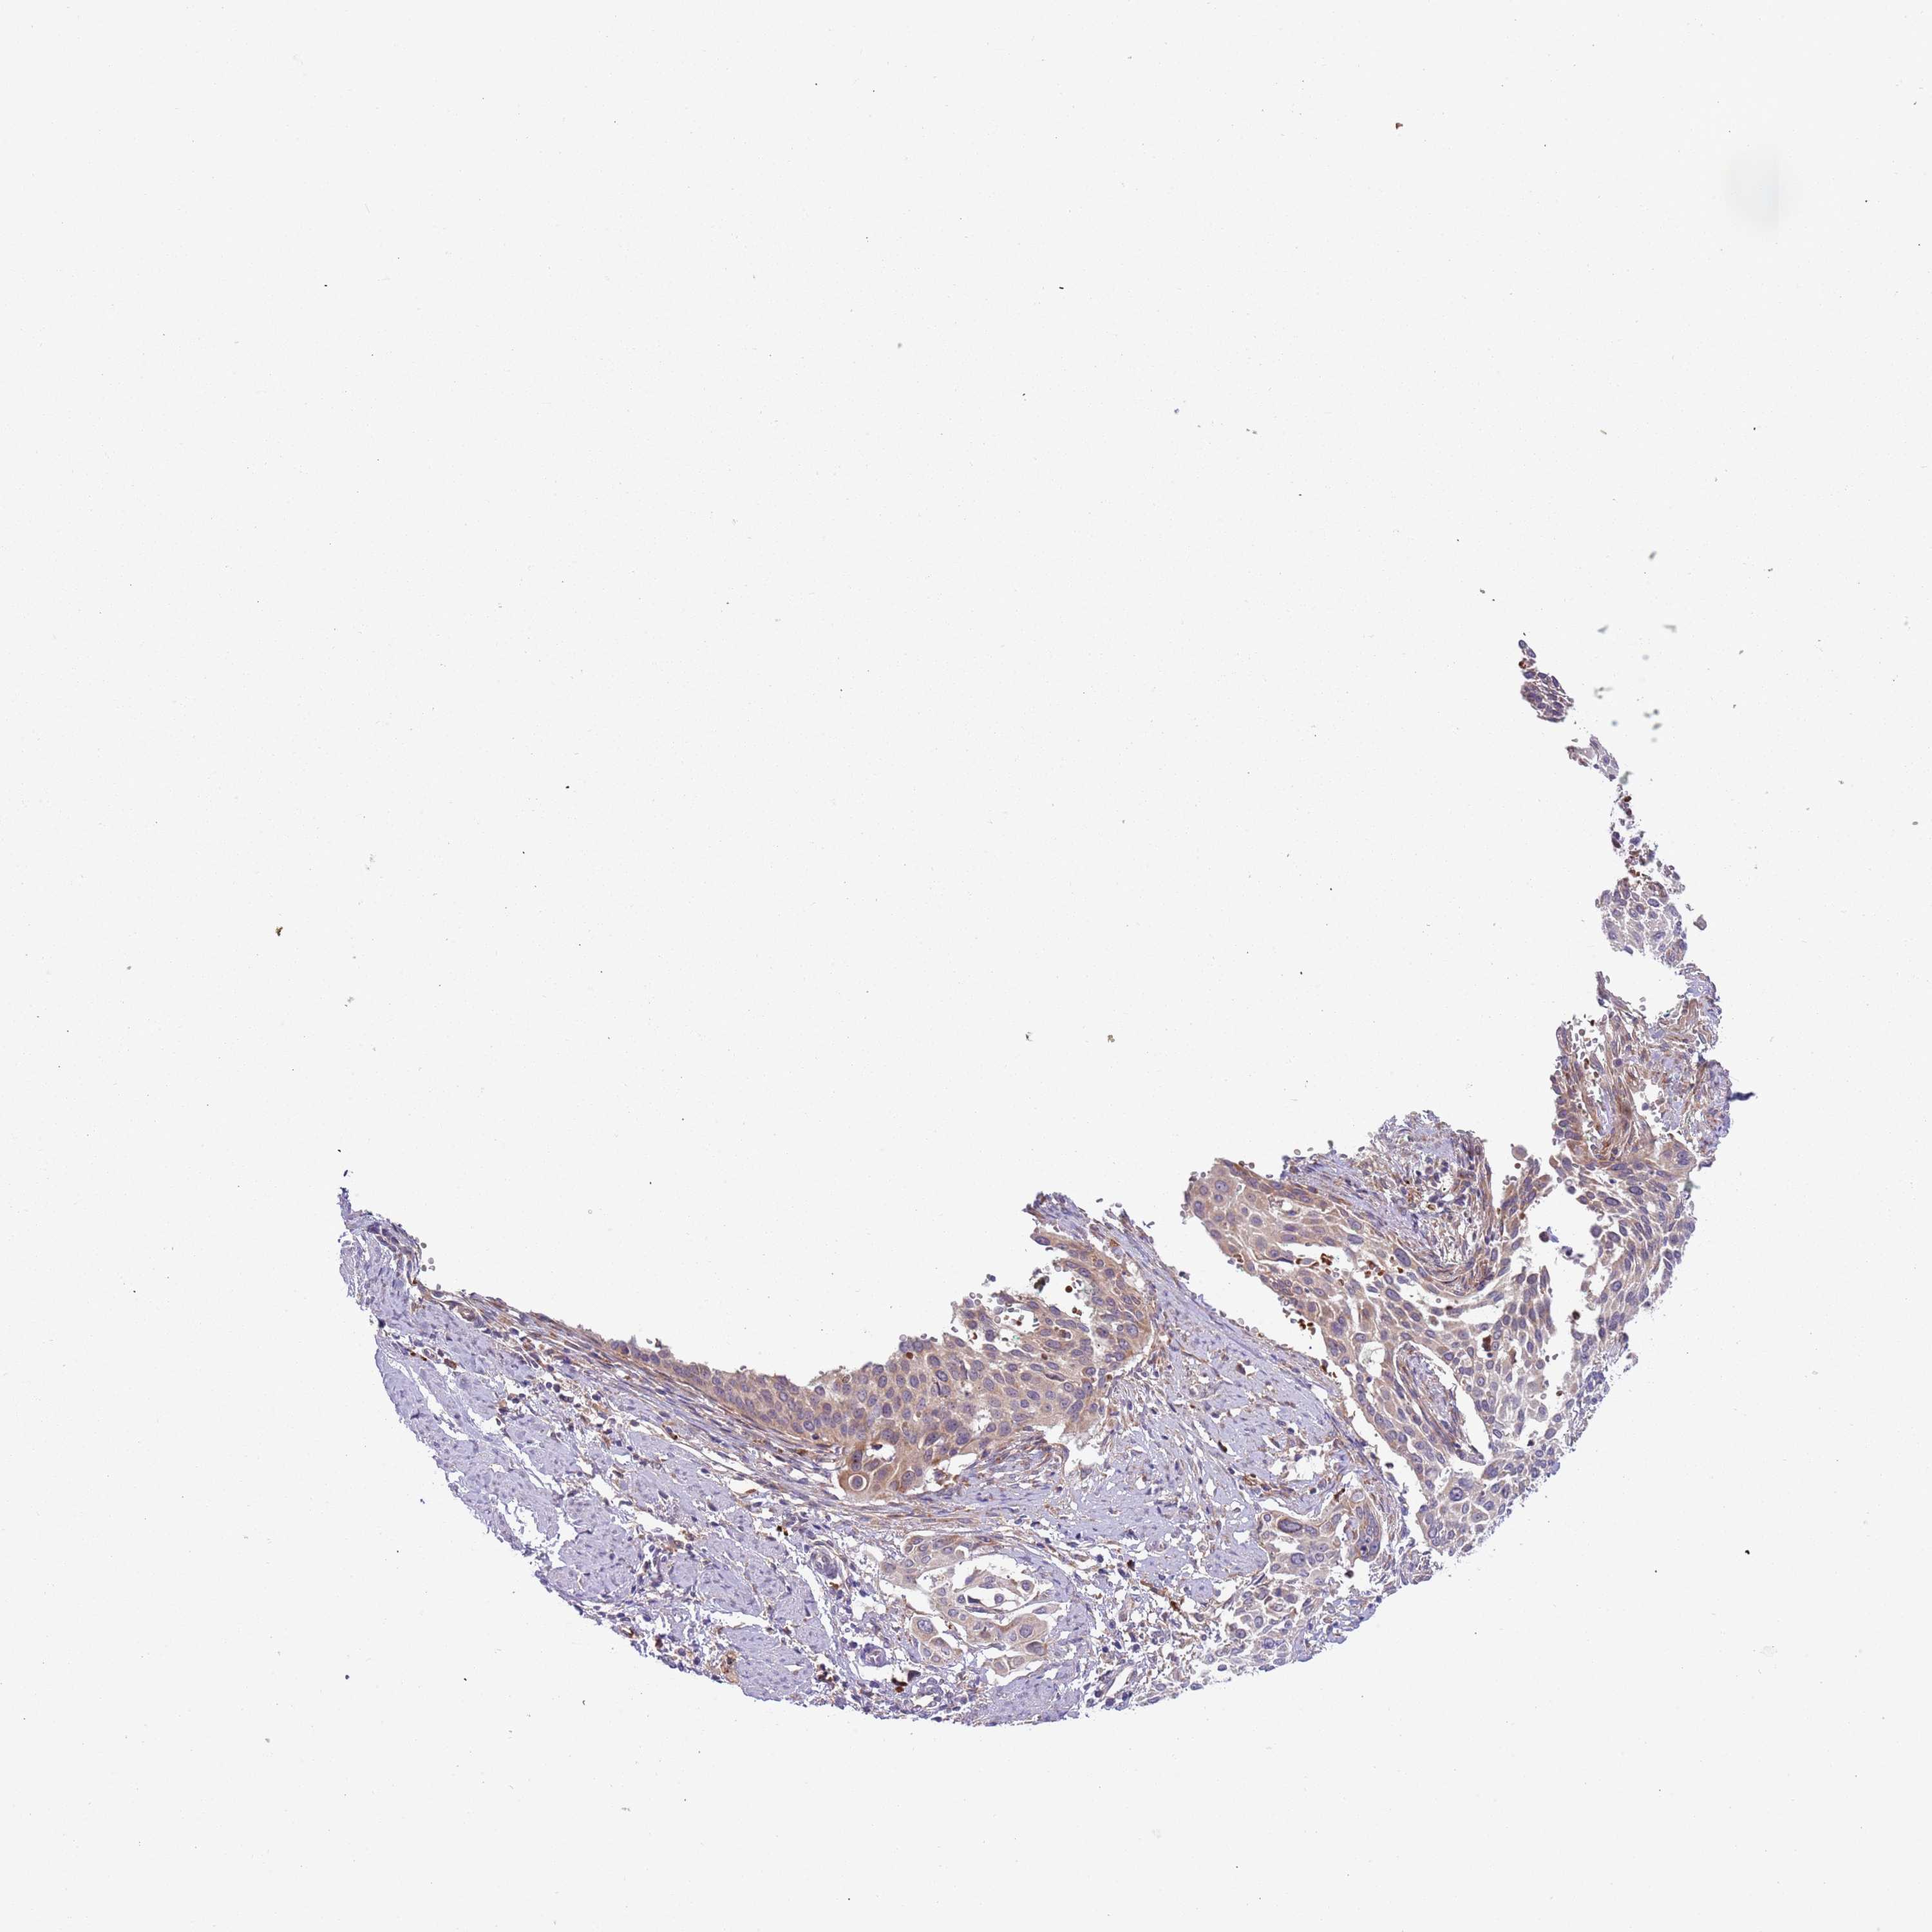

CERVICAL CANCER - Protein expressioni

A mouse-over function shows sample information and annotation data. Click on an image to view it in a full screen mode. Samples can be filtered based on level of antibody staining by selecting one or several of the following categories: high, medium, low and not detected. The assay and annotation is described here.

Note that samples used for immunohistochemistry by the Human Protein Atlas do not correspond to samples in the TCGA dataset.

Antibody stainingi

Antibody staining in the annotated cell types in the current human tissue is reported as not detected, low, medium, or high, based on conventional immunohistochemistry profiling in selected tissues. This score is based on the combination of the staining intensity and fraction of stained cells.

Each image is clickable and will lead to virtual microscopy that enables deeper exploration of all samples and also displays staining intensity scores, fraction scores and subcellular localization as well as patient and tissue information for each sample.

Antibody HPA040401

Antibody HPA043921

Staining

High

Medium

Low

Not detected

Intensity

Strong

Moderate

Weak

Negative

Quantity

>75%

75%-25%

<25%

None

Location

Nuclear

Cytoplasmic/membranous

Cytoplasmic/membranous,nuclear

Squamous cell carcinoma, NOS

Adenocarcinoma, NOS